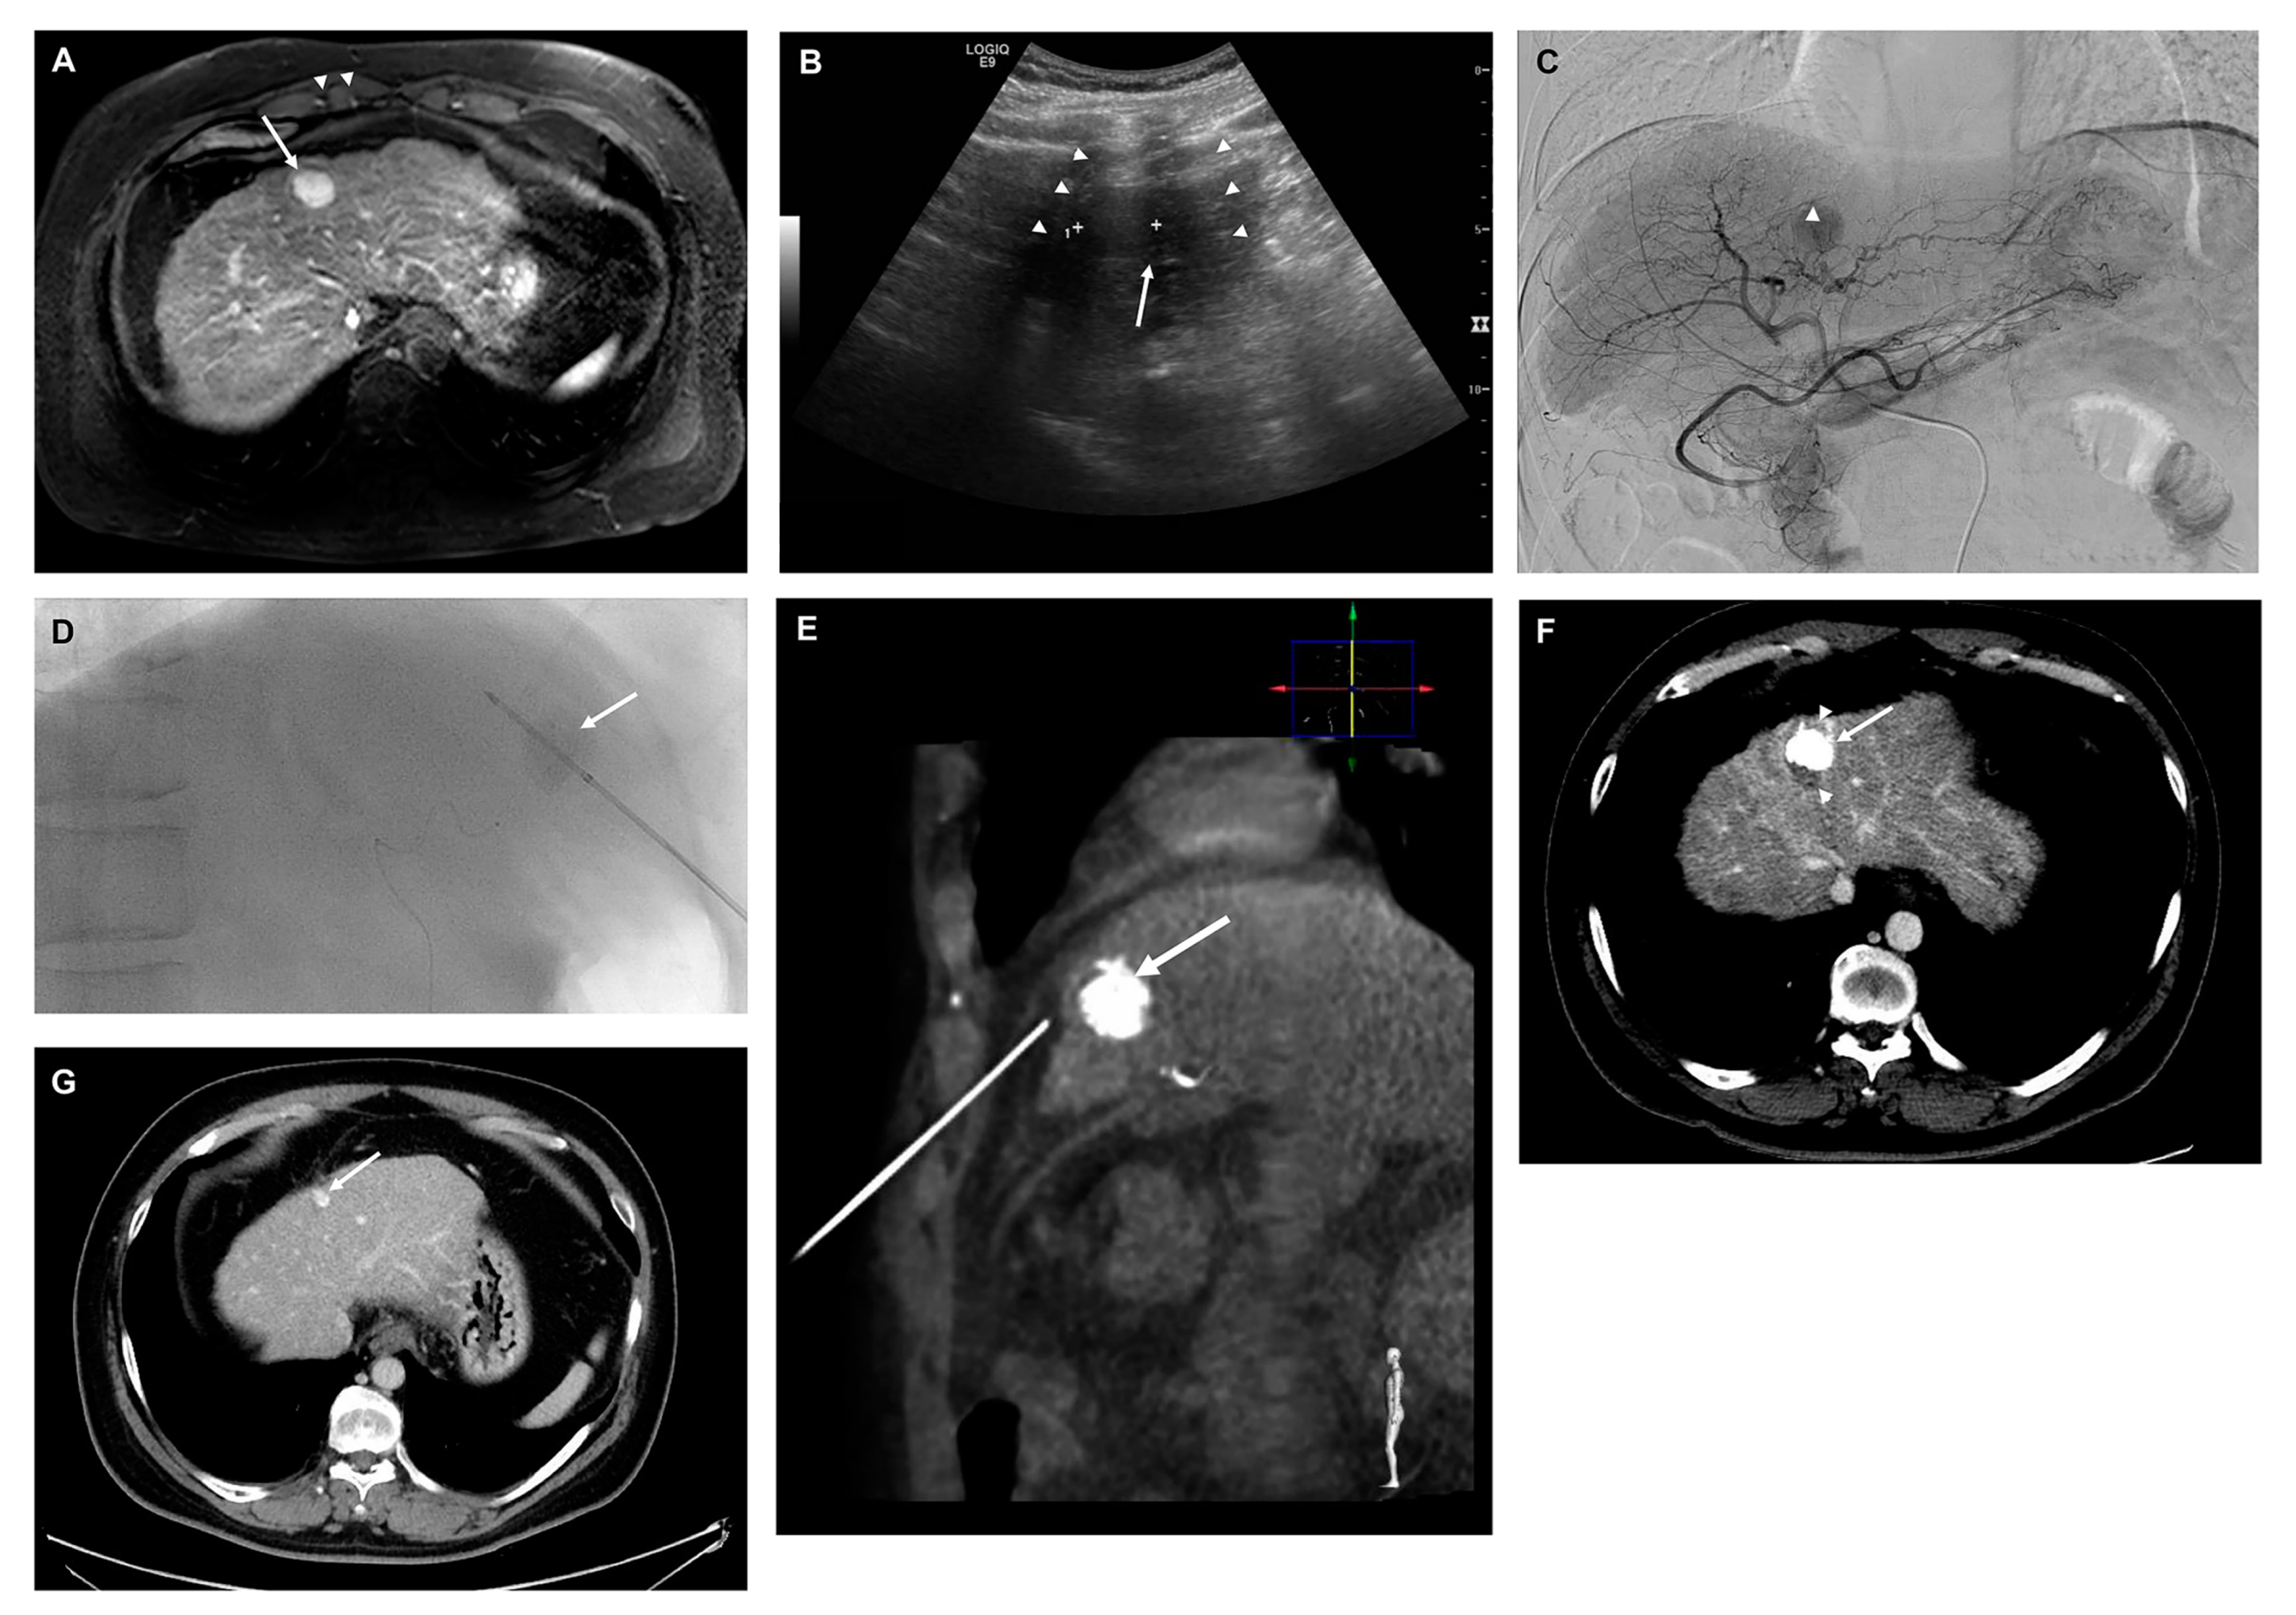

2.4. TACE + RFA and RFA Procedure and Follow-Up Protocol after Treatment

2.5. Outcome Assessment